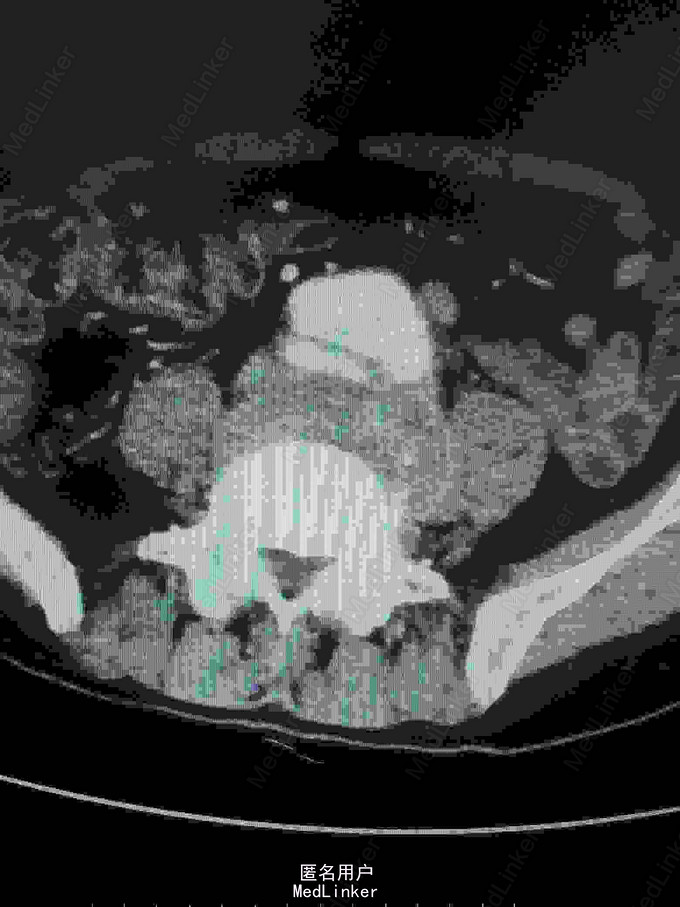

主诉:腰腹痛7月,加重一周。 病史:七月前发热后开始出现腰腹痛,呈持续性撕裂样痛,伴腹胀,症状反复。一周前腹痛症状加重。

体查:下腹部可触及搏动性包块。 辅助检查:腹部CT:腹主动脉假性动脉瘤并血栓形成,腰5椎体受侵蚀。血培养:沙门氏菌。

诊断:沙门氏菌感染性腹主动脉假性动脉瘤 处理:急诊行腹主动脉瘤切除人工血管置换术,术后予美罗培南抗感染8周,续以左氧氟沙星口服。